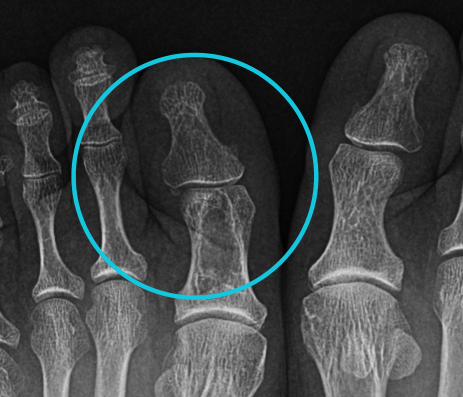

45 YO F. Recently developed knee pain.

• Popcorn like lesion, stippled at proximal tibia.

Think:

• Enchondroma. (Painless)

• Chondrosarcoma (because Pain)